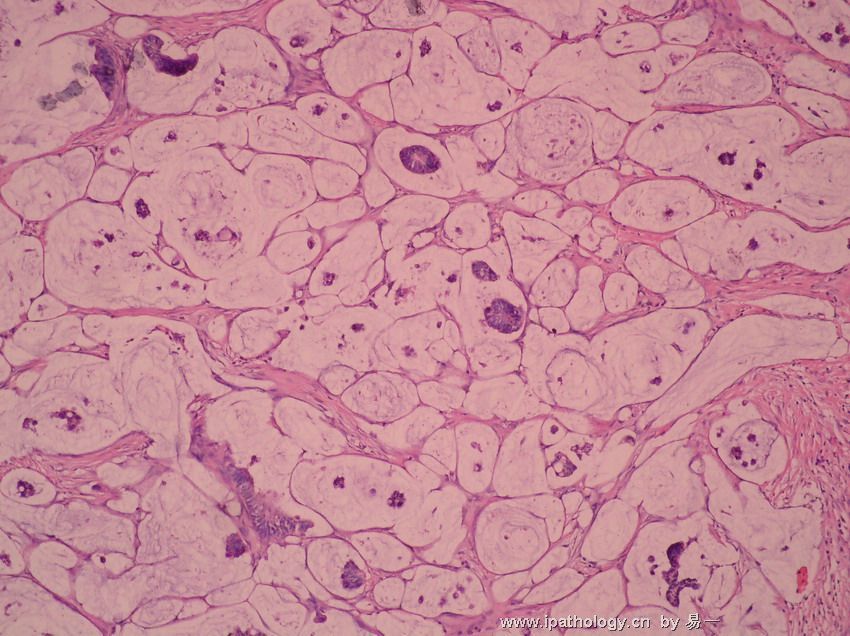

慢性盆腔炎患者全身症状多不明显,一般仅为程度不同的、时轻时重的下腹疼痛,或下腹坠胀或牵扯感,月经前、劳累后或性交后加重,并常伴有大便时的腹坠感,白带增多、腰痛、月经失调等,也可因输卵管粘连造成宫外孕或不孕症。慢性盆腔炎常为急性盆腔炎未能彻底治疗,或患者体质较差,病程迁延所致。

它可使机体发生慢性输卵管炎与输卵管积水、输卵管卵巢炎及输卵管卵巢囊肿、慢性盆腔结缔组织炎。慢性盆腔炎的症状特点是:其病慢,病程长。全身症状多不明显,可有低热,易感疲乏,伴下腹坠腰痛等。检查时发现,子宫常呈后位,活动受限,或粘连固定。慢性盆腔炎的主要鉴别诊断有:子宫内膜异位症和卵巢癌。

女性朋友们如果出现低热、易感疲劳、失眠、精神不振、周身不适等情况时,就有可能是盆腔炎的症状了,下腹部坠胀、疼痛及腰骶部酸痛,会常在劳累、性交后、月经前后加剧。由于慢性炎症而导致盆腔淤血、月经过多,卵巢功能损害时,会出现月经失调,输卵管黏连阻塞时,会导致不孕症。